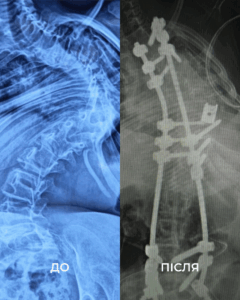

З роками стан лише погіршувався: невпинний біль, задишка, неможливість довго сидіти. Хребет дитини викривився аж на 160 градусів. Вдома дівчинка пересувалася з ходунцями, у школі – на кріслі колісному. Часто бувала в лікарнях та на реабілітації.

«Щоб виправити її сколіоз, нам потрібно було видалити цілий хребець. У перший день операції ми закріпили її хребет гвинтами. А вже на другий день – видалили кілька ребер, ізолювали спинний мозок та встановили титанову клітку для підтримки хребта. А потім повільно виправляли її разом з моєю колегою, нейрофізіологинею Меган Маллані», – розповідає американський ортопед-травматолог Марк Диржка. Після двох операцій, 18 годин наркозу та через надто слабкі м’язи, два наступні тижні Віка пробула в реанімації під киснем. Але результат того вартував – хірургам вдалося вирівняти хребет дівчинки на 85%.

Ось що каже мама Віки: «Спина дійсно змінилася. Немає більше того горбу з ребер. Вона витягнулася, стала вища. Ми здивовані! І лікарі самі сказали, що зробили більше, ніж очікували».